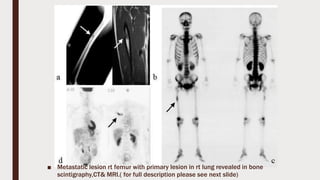

■ Metastatic lesion rt femur with primary lesion in rt lung revealed in bone

scintigraphy,CT& MRI.( for full description please see next slide)

■ A case of bone metastasis located in the middle of femur (patient

#1). Fifty-year-old male patient with lung cancer. At first, the lesion

was suspected to be a primary femoral bone tumor. Then the

diagnosis was changed to metastatic tumor based on the result of

biopsy, which showed a poorly- differentiated carcinoma. Plain X-ray

and MRI (T1WI) showed an excentric bone tumor in the right femoral

diaphysis (a, b). BS showed high accumulation of 99m Tc-HMDP in

the corresponding area (c). FDG-PET was performed to detect the

primary tumor, and therefore, FOV of PET scan did not include full-

length of the femur. Whole-body scan from inguinal area to face

showed high accumulation of FDG in the right upper lobe which was

diagnosed as lung cancer later